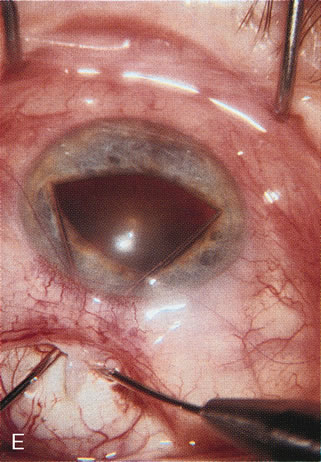

CASE 6: ANTICIPATED LENS EXTRACTION POST FAILED TRABECULECTOMY WITH ADVANCED DISC DAMAGE AND IOP OUTSIDE TARGET PRESSURE RANGE

The inflammation associated with lens extraction at any site usually causes complete failure of a marginal functioning bleb. In addition, pressure reduction by medical means is usually minimal in these recalcitrant cases, and combined surgery is indicated. In the past, these cases were approached with large-incision ECCE, clear corneal cataract incision, and bleb revision. Drawbacks included those mentioned earlier for large incision clear corneal cataract extraction, and bleb revision is often associated with conjunctival buttonholes, wound leaks, subconjunctival hematoma, destruction of friable sclera, and associated hypotony. With the advent of modern-day cataract surgery, a phacotrabeculectomy is often possible adjacent to the failed filter (Fig. 7). The ability to combine cataract extraction with implant and filtration surgery all through the same small incision has greatly improved outcomes for patients with marginal preoperative filters. There are several other viable options in this case. If the surgeon elects to remove the cataract through a temporal clear corneal incision, the bleb may be revised or a new adjacent filter fashioned. As mentioned earlier, revising a failed filter is technically challenging. If the surgeon believes it is not feasible to revise the filter or fashion a new one, a glaucoma drainage implant is a reasonable option combined with temporal lens extraction.172

Fig. 7. Phacotrabeculectomy adjacent to a failed filter in cataractous eye. The ability to combine small-incision cataract extraction with trabeculectomy all through the same incision adjacent to the failed filter allows the surgeon to work in a familiar superior area. Avoiding incisions into the existing bleb decreases conjunctival buttonholes, hypotony, operating room time, and subconjunctival bleeding. A. Appearance of failed bleb with exposure of superior temporal quadrant gained with a corneal traction suture. B. Prepare a limbus-based conjunctival flap and a scleral flap. C. This bleb is at high risk to fail again justifying the need for MMC, 0.2 mg/cc applied on a pledget for 4 minutes. D. Insert the keratome and perform phacotrabeculectomy in the usual fashion.